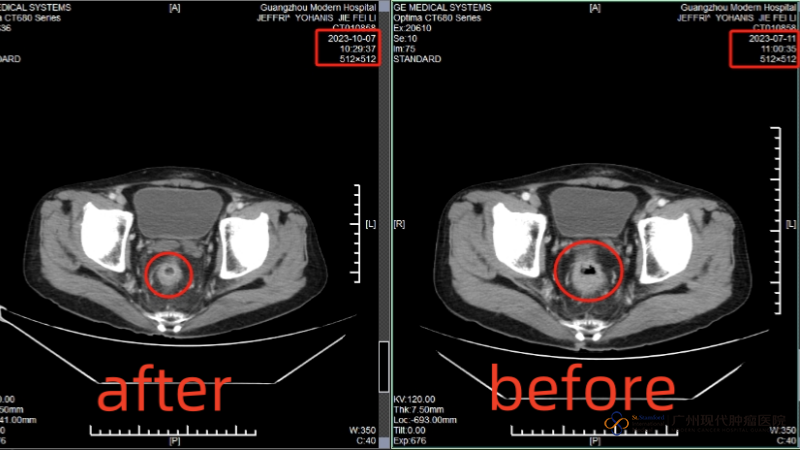

After I arrived at the hospital, the MDT medical team of the hospital consulted me and formulated a comprehensive treatment of "intervention + cryotherapy". Before the treatment, the tumor in the anus was about 29mmx38mm, but after an intervention, the tumor was reduced to 13mmx17mm, and the multiple metastatic foci in the liver were mostly invisible on CT after cryotherapy. Both my wife and I are very happy with this result.

[Comparison of rectal tumor sizes after the first interventional therapy]